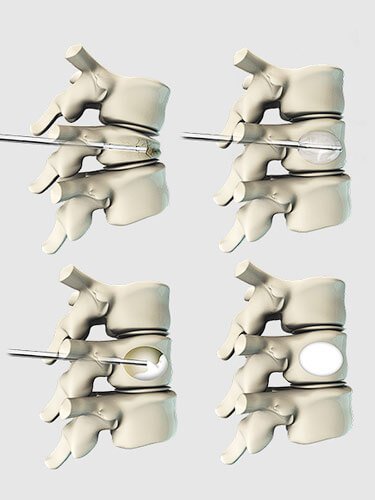

É feita uma incisão de aproximadamente 1 cm de comprimento. Usando uma agulha e a cânula (tubo), o especialista em coluna cria um pequeno caminho para dentro do osso fraturado. Um balão pequeno é guiado através do tubo no interior da vértebra. O procedimento é feito em ambos os lados do corpo vertebral.

Em seguida, os balões são inflados com cuidado em uma tentativa de aumentar as vértebras em colapso e devolvê-las à sua posição pré-fratura.

Numa tentativa para criar um vazio (cavidade), os balões são insuflados no corpo vertebral. Uma vez que o corpo vertebral se encontra na posição correta, o balão é esvaziado e retirado.

A cavidade é preenchida com cimento ósseo.